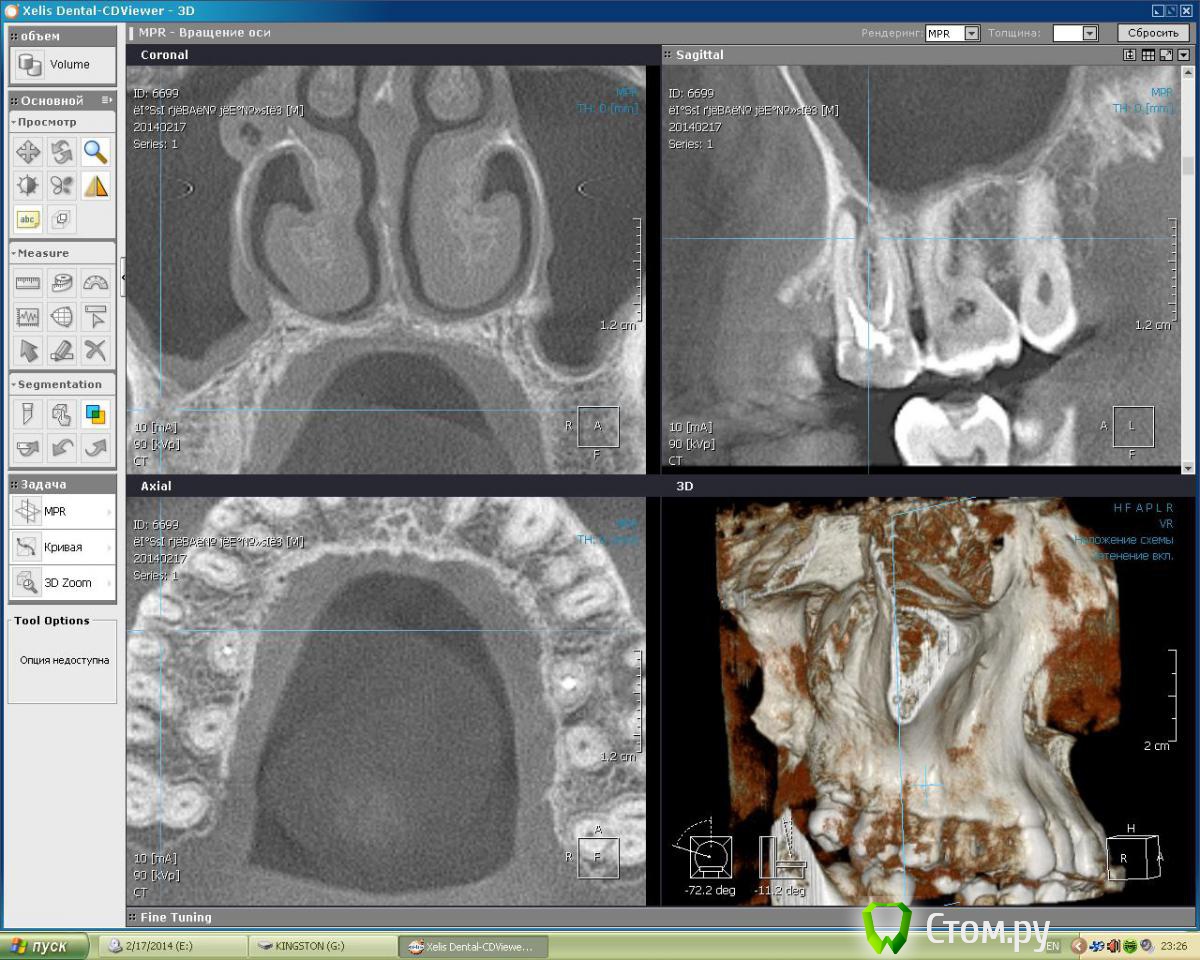

Dtm Опубликовано 1 марта, 2014 Автор Поделиться Опубликовано 1 марта, 2014 Подниму немного свою тему - сделал наконец то КТ, кажется я не ошибался в своих подозрениях на обе верхние 6-ки, что скажут уважаемые доктора? Ссылка на комментарий

Гарриевич Опубликовано 2 марта, 2014 Поделиться Опубликовано 2 марта, 2014 Подниму немного свою тему - сделал наконец то КТ, кажется я не ошибался в своих подозрениях на обе верхние 6-ки, что скажут уважаемые доктора?Нужно перелечивать Ссылка на комментарий

IvanK Опубликовано 3 марта, 2014 Поделиться Опубликовано 3 марта, 2014 Нужно перелечивать +1 Ссылка на комментарий

Dtm Опубликовано 3 марта, 2014 Автор Поделиться Опубликовано 3 марта, 2014 Спасибо! На КТ видно что верхушки корней 6 контактируют с ВЧ пазухой - насколько велик риск при перепломбировании (я правильно понял?) вывести пломбировочный материал за верхушку корня в пазухи в данном случае? Ссылка на комментарий

IvanK Опубликовано 3 марта, 2014 Поделиться Опубликовано 3 марта, 2014 При грамотном подходе проблем быть не должно. Всякое бывает Ссылка на комментарий

Dtm Опубликовано 3 марта, 2014 Автор Поделиться Опубликовано 3 марта, 2014 Согласен, но для меня как пациента это имеет решающее значение - последствия могут быть неприятные. Может быть безопаснее удалить с имплантацией в перспективе? На левой 6 явно киста у корня? Насколько реально ее пролечить и как, просто сменить пломбу думаю не все, терапия какая то нужна в процессе, я имею ввиду вскрыть, ввести лекарство например? Ссылка на комментарий